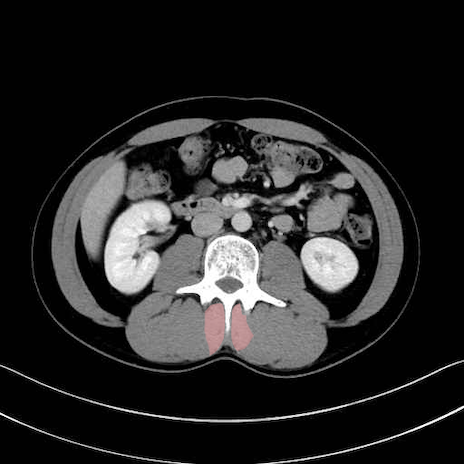

多裂筋 (Multifidus)